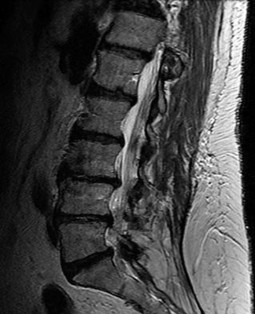

On a sagittal MRI of the lumbar spine, a vertebral body endplate adjacent to a degenerated disc shows hypointense signal on T1-weighted images and hyperintense signal on T2-weighted images. This finding corresponds to which Modic type, and what does it pathologically represent?